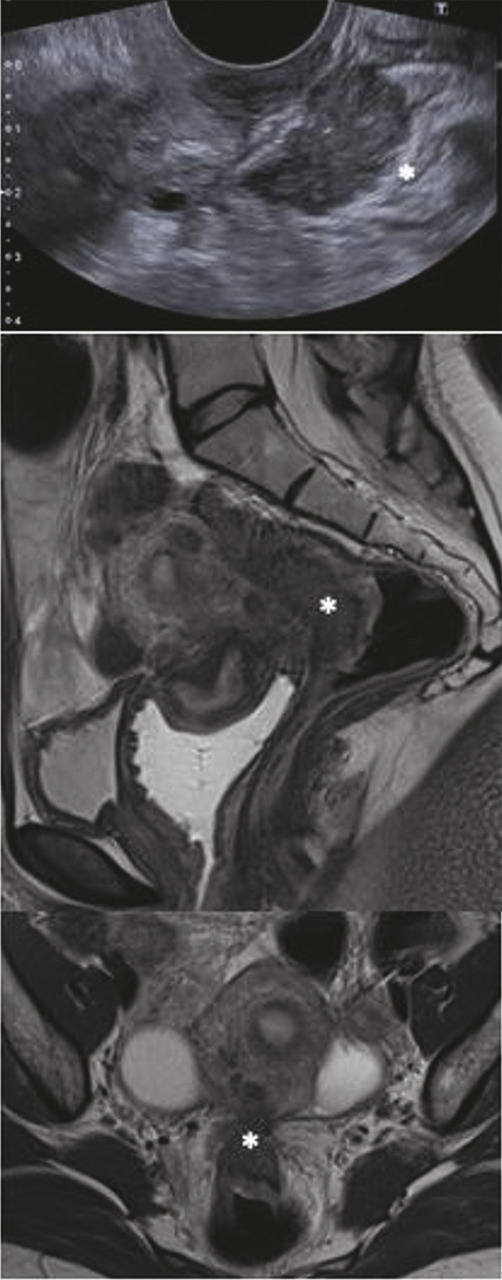

Une fois le diagnostic évoqué, des examens complémentaires non invasifs s’imposent. Trois examens font référence pour étudier la progression en profondeur de l’endométriose, à savoir l’imagerie par résonance magnétique (IRM) pelvienne, l’échographie transvaginale (ETV) et l’écho-endoscopie rectale (EER). Ils doivent être réalisés par des opérateurs entraînés.

De nombreuses méta-analyses comparent les différentes techniques d’imagerie en étudiant les méthodologies et les performances.11 Ces dernières varient en fonction de la localisation de l’endométriose. L’IRM paraît être l’examen le plus complet en cas d’endométriose profonde, notamment pour effectuer le bilan d’extension et surveiller l’évolution de la maladie. Elle est souvent prescrite en cas de suspicion clinique et/ou échographique.

Une méta-analyse a comparé les résultats préopératoires des différentes imageries non invasives (ETV, IRM, EER et scanner pour poser le diagnostic de l’endométriose rectosigmoïdienne) aux données chirurgicales, considérées comme le gold standard.12 Elle conclut que la sensibilité de l’EER semble un peu supérieure à celle de l’IRM (92 % vs 86 %). Les spécificités de l’IRM et de l’ETV étaient excellentes (97 % et 96 %). Les auteurs estiment que l’ETV peut être intéressante en première ligne, par sa faisabilité et son accessibilité en pratique clinique.

Réaliser plusieurs examens complémentaires augmente de façon importante la sensibilité diagnostique. En effet, selon une étude qui a porté sur 407 patientes,14 associer l’IRM et l’écho-endoscopie rectale pour poser le diagnostic d’endométriose colorectale augmentait la sensibilité de détection de 10 %, et le diagnostic était confirmé en peropératoire dans 100 % des cas lorsque les deux examens étaient concordants (figure ).15